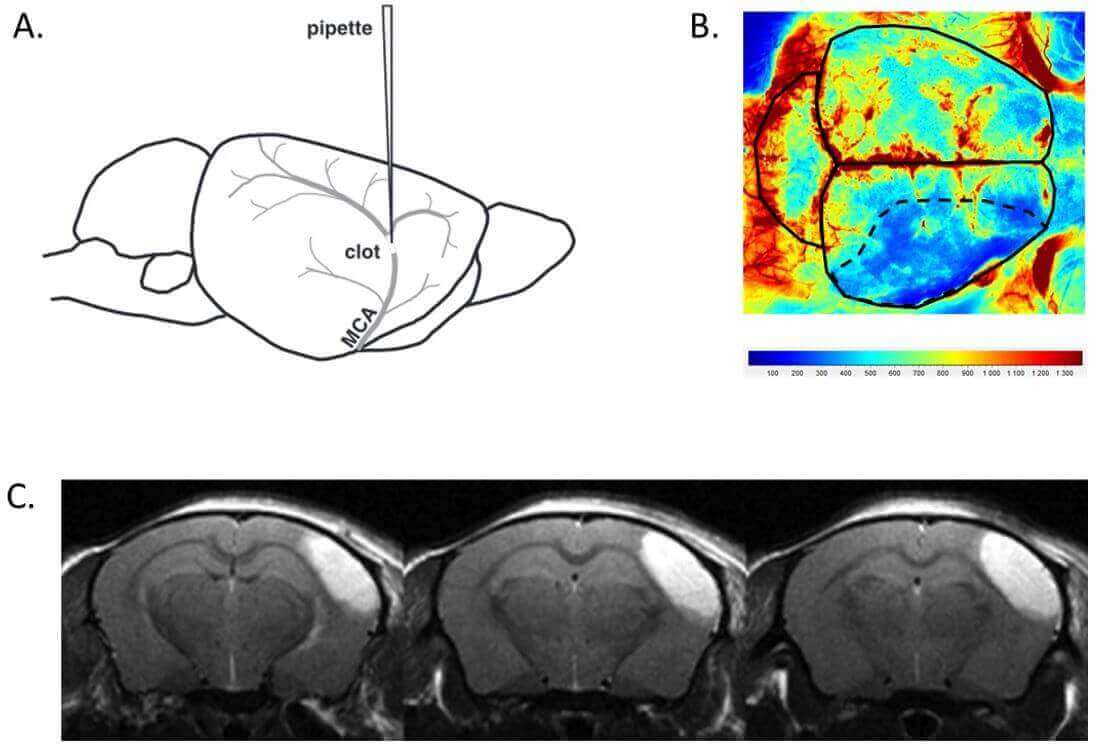

In situ thromboembolic stroke is induced by the injection of purified thrombin in the Middle Cerebral Artery (MCA) at M1/M2 bifurcation, modelling a distal thrombosis eligible for thrombolytic treatments in humans. It results in reproducible ischemic lesions in the somatosensory cortex (≈20 mm3 ; Fig. 1). Moreover, it produces a significant strength deficit of the contralateral paws, lasting up to 14 days after stroke onset thus allowing functional recovery studies.

Figure 1. A. Thrombin injection in the MCA at M1/M2 bifurcation; B. Cerebral blood flow reduction in the ischemic hemisphere at stroke onset (laser speckle imaging); C. Representative lesion at 24h after stroke onset in saline-treated mice (T2* MRI).